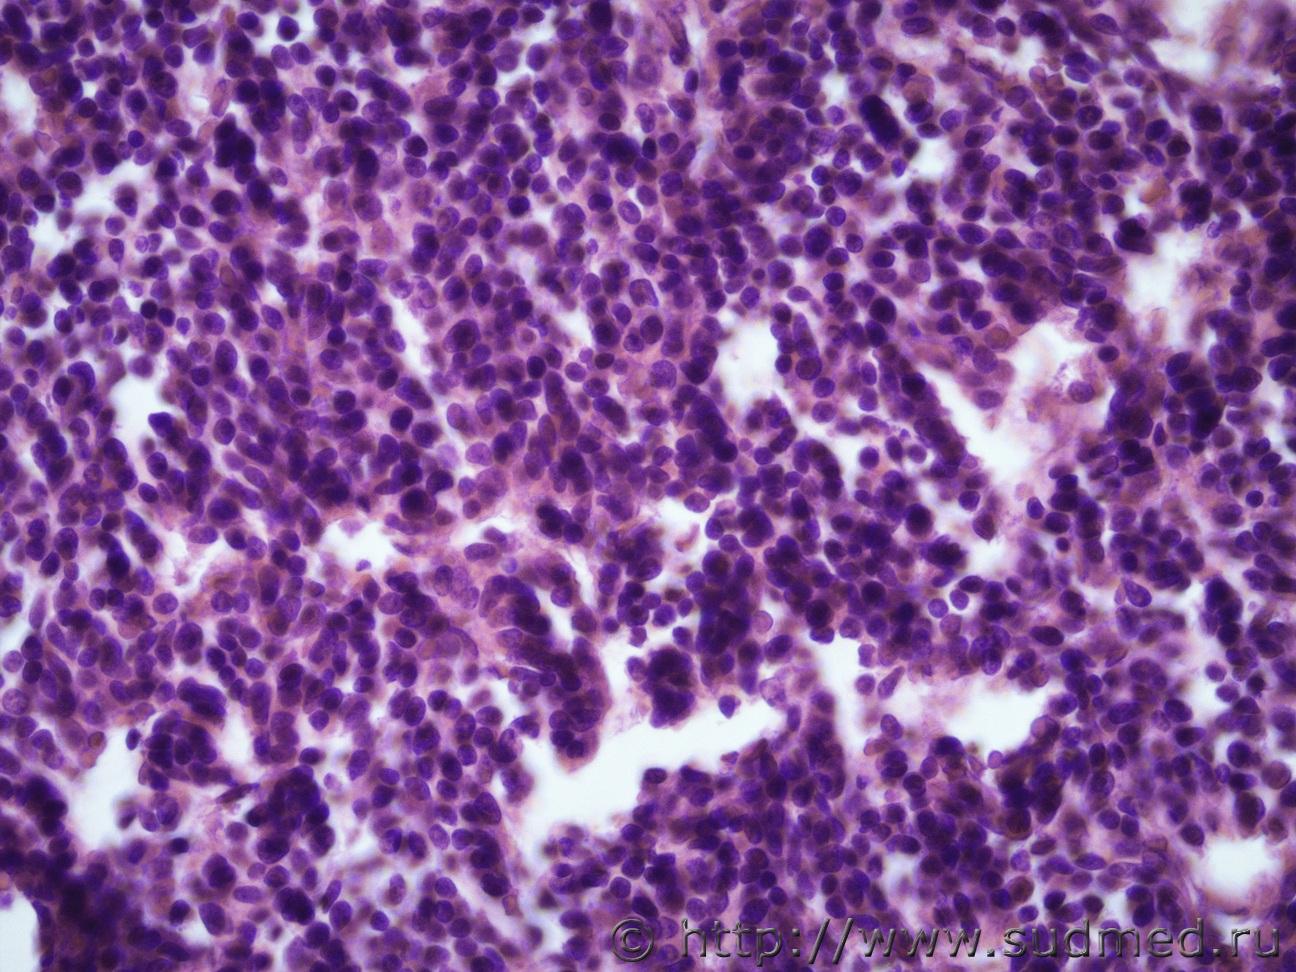

Ув. коллеги и снова здравствуйте. Как всегда опухоль. Макро- опухоль поджелудочной железы с прорастанием в окружающую клетчатку с метастазами в перибронхиальные, перипортальные ЛУ, в прикорневые отделы легких, в стенку желчного пузыря, тонкого кишечника. Легкие Судебная медицина - Прикрепленное изображение Судебная медицина - Прикрепленное изображениеСудебная медицина - Прикрепленное изображениеСудебная медицина - Прикрепленное изображение, перибрЛУСудебная медицина - Прикрепленное изображение ПЖ Судебная медицина - Прикрепленное изображениеСудебная медицина - Прикрепленное изображение , печеньСудебная медицина - Прикрепленное изображение Судебная медицина - Прикрепленное изображение Судебная медицина - Прикрепленное изображение Судебная медицина - Прикрепленное изображение Судебная медицина - Прикрепленное изображение, тонк кишСудебная медицина - Прикрепленное изображение

Наиболее подходит нейроэндокринный рак

Спасибо, рассмотрю этот вариант. Я все думала может НД протоковая аденокарцинома или мелкоклеточный рак.

Солидарен.

Непохоже.